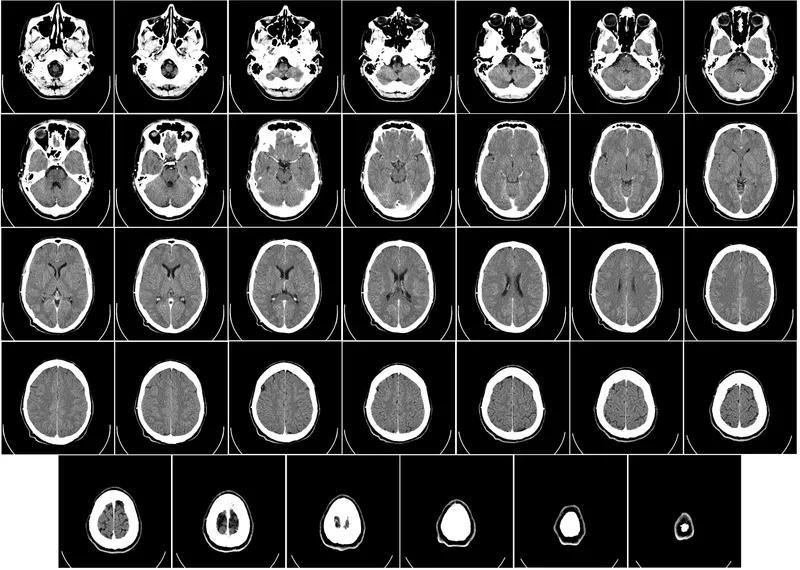

Neuroplasticity allows your brain to reorganize itself by forming new neural connections throughout life. This means that even if you've been living with chronic pain, your brain can learn to perceive it differently.

One effective way to harness this power is through cognitive behavioral therapy, or CBT. Studies suggest that CBT is associated with changes in how the brain processes pain signals, potentially diminishing the sensation of pain.